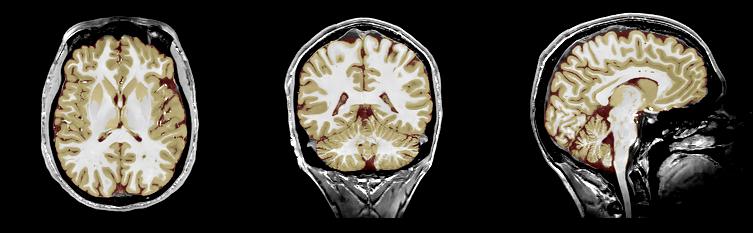

MRI Brain Segmentation

In this page we present some of our approaches for MR Brain segmentation.

seg